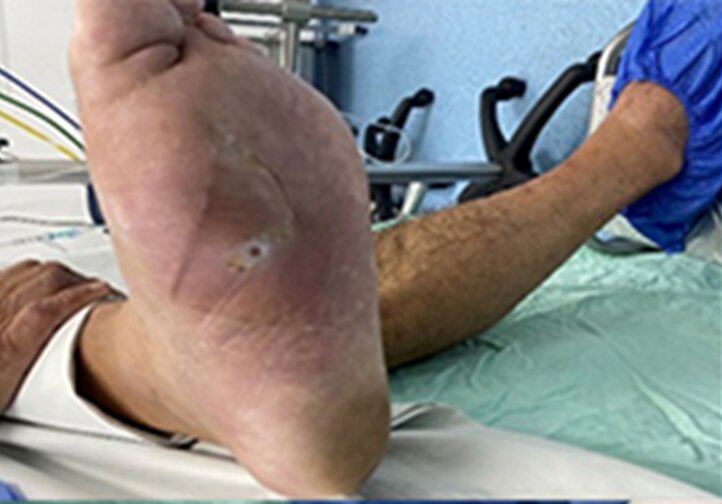

59-летний пациент поступил в отделение гнойной хирургии с жалобами на боли в левой стопе. При осмотре и пальпации был обнаружен отек, связанный с воспалительными изменениями на медиальной и дистальной областях подошвенной поверхности стопы. Проведено комплексное обследование, включая рентгенологическое и КТ стопы. Выявлена деструкция головки и диафиза первой плюсневой кости, а также и проксимальной головки основной фаланги. Результаты соответствующих лабораторных исследований показали, что уровень гликированного гемоглобина (HbA1c) составил 8,2.

В анамнезе была обнаружена медиальная подошвенная язва, которую неоднократно лечили в разных учреждениях, но без благоприятного клинического результата. На основании анамнеза и результатов параклинических исследований было принято решение о проведении хирургического вмешательства — радикальной обработки гнойно-некротического очага, включая остеотомию первой плюсневой кости от середины до головки и основной фаланги.